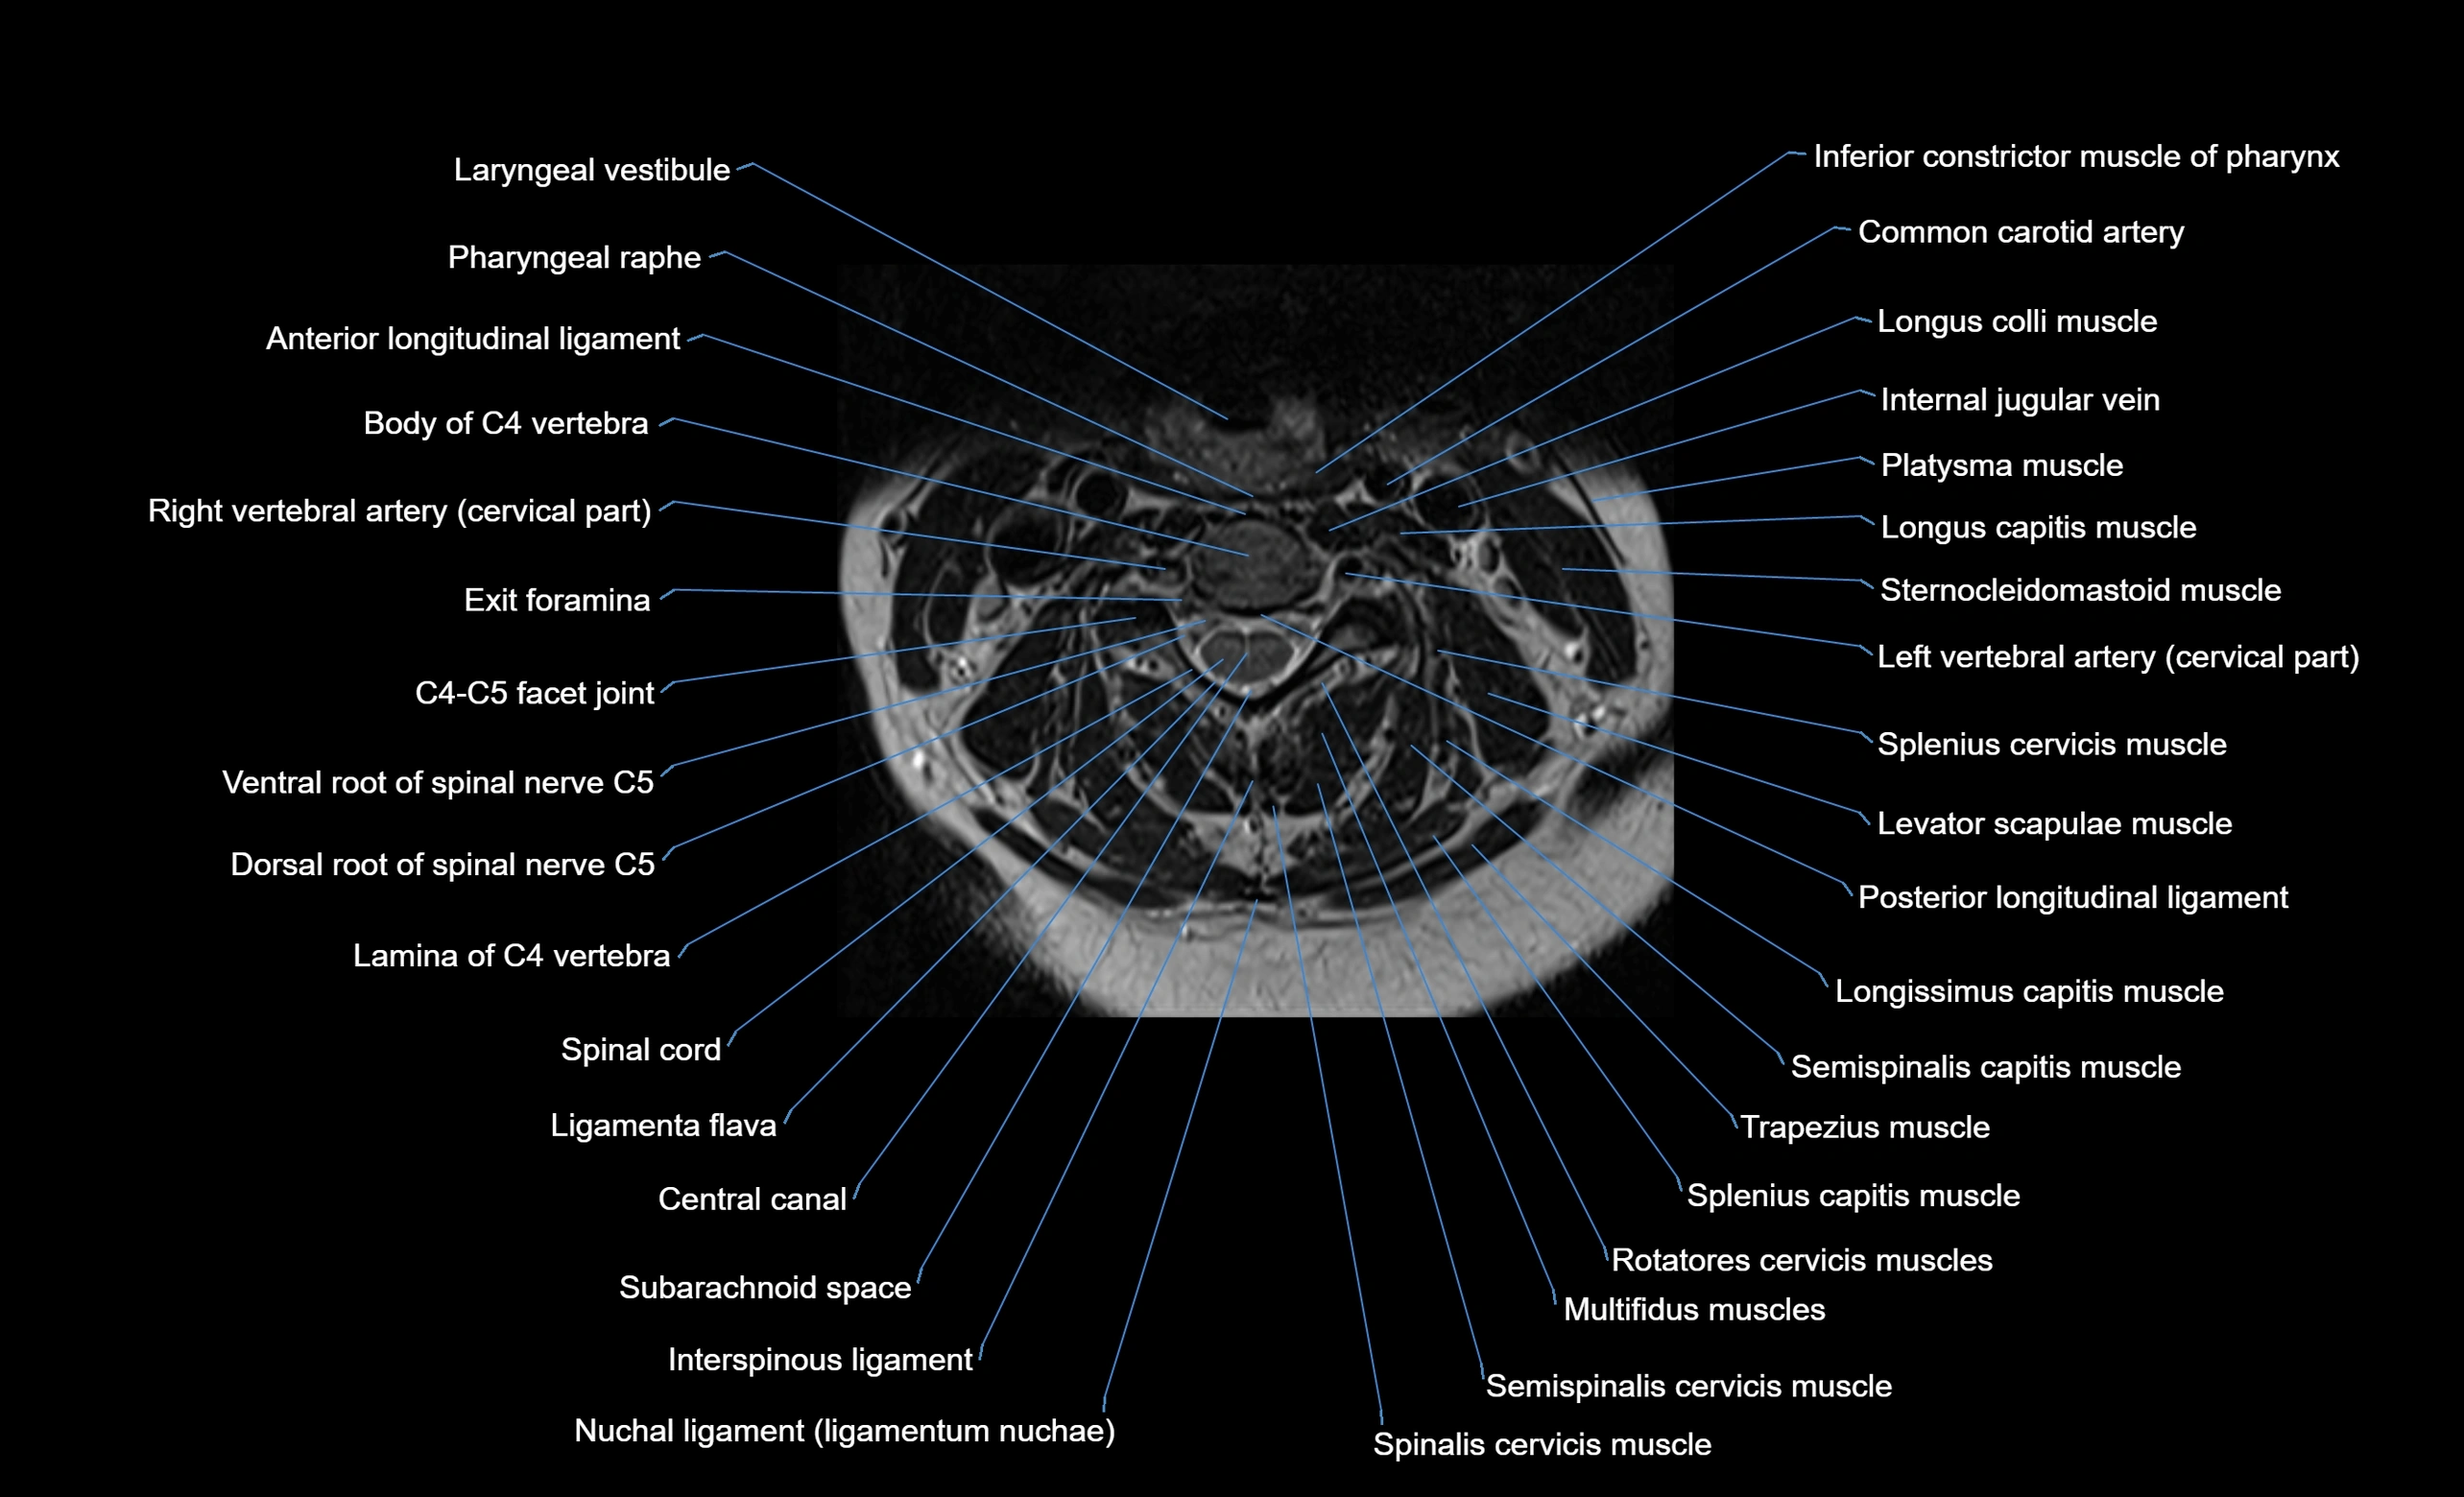

MRI appearance

T1-weighted images:

• Annular epiphysis: Low signal cortical rim at the vertebral margin

• Adjacent marrow: Intermediate-to-high signal in the vertebral body

• Disc interface: Clear delineation between bone and annulus

T2-weighted images:

• Annular epiphysis: Low signal intensity line

• Endplate cartilage (in younger patients): Intermediate signal

• Intervertebral disc: High signal nucleus pulposus

STIR:

• Annular epiphysis: Low signal cortical rim

• Adjacent marrow: Suppressed fat signal with preserved bony outline

• Utility: Highlights marrow and endplate interface in developing spine

MRI image

image